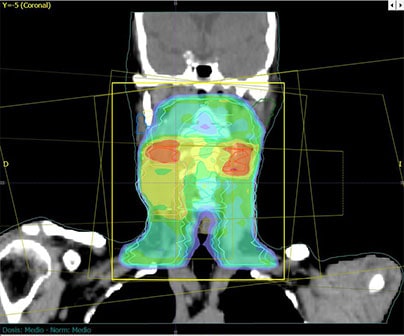

Radioterapia de intensidad modulada (IMRT)

La Radioterapia de Intensidad Modulada es una técnica moderna que permite mediante el uso de haces de radiación de intensidad variable, tratar múltiples volúmenes tumorales a diferentes dosis y en forma muy precisa, entregando baja dosis en el tejido sano durante cada fracción de tratamiento.

La IMRT es una modalidad aún más precisa que la radioterapia 3-D, ya que permite irradiar tumores con un mínimo daño al tejido sano mediante la utilización de diferentes incidencias de campos con intensidad de dosis no uniformes en el volumen tumoral, lo que nos permite la reducción del volumen de tejido sano expuesto a dosis altas de irradiación y escalar dosis en el tumor con mínima toxicidad aguda.

La técnica consiste en dividir el haz de tratamiento en cientos de pequeños haces independientes cada uno con intensidad variable e irradia al paciente desde ángulos y ubicaciones más favorables.

- Posibilita obtener distintos niveles de dosis en un mismo campo de irradiación, lo que permite maximizar la dosis en el volumen tumoral y minimizar la dosis en los órganos a riesgo; aumentando las posibilidades de control local y sobrevida disminuyendo las toxicidades agudas y crónicas.